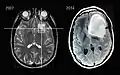

Imágenes por resonancia magnética de un paciente con astrocitoma, que muestran la progresión del tumor en el transcurso de siete años